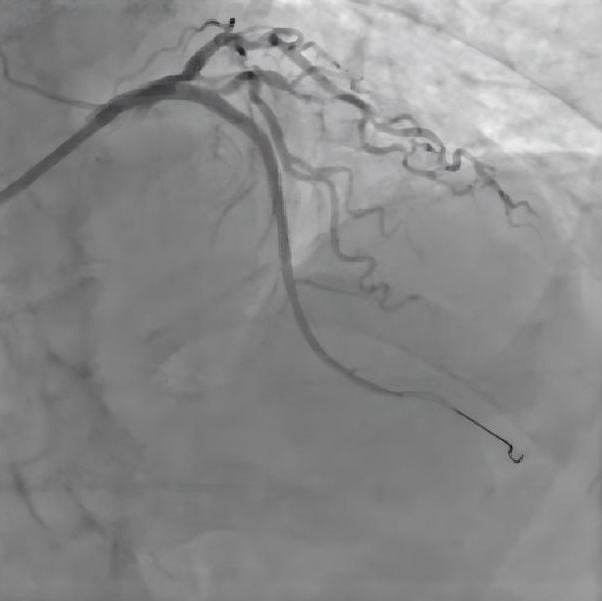

支架植入后造影